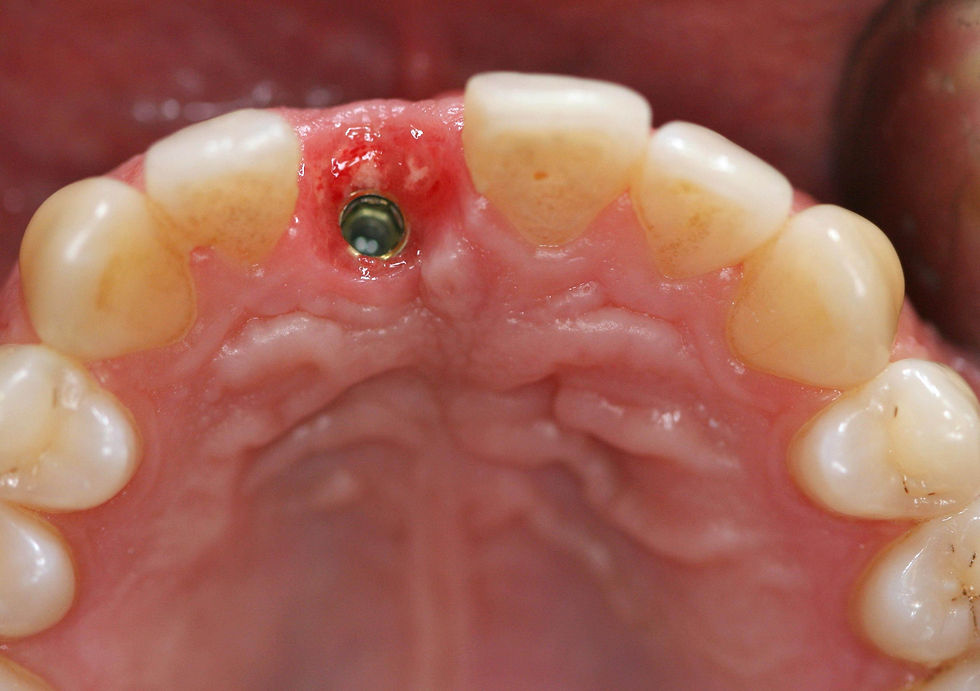

Frontal view after the positioning of the immediate screw-retained temporary crown.